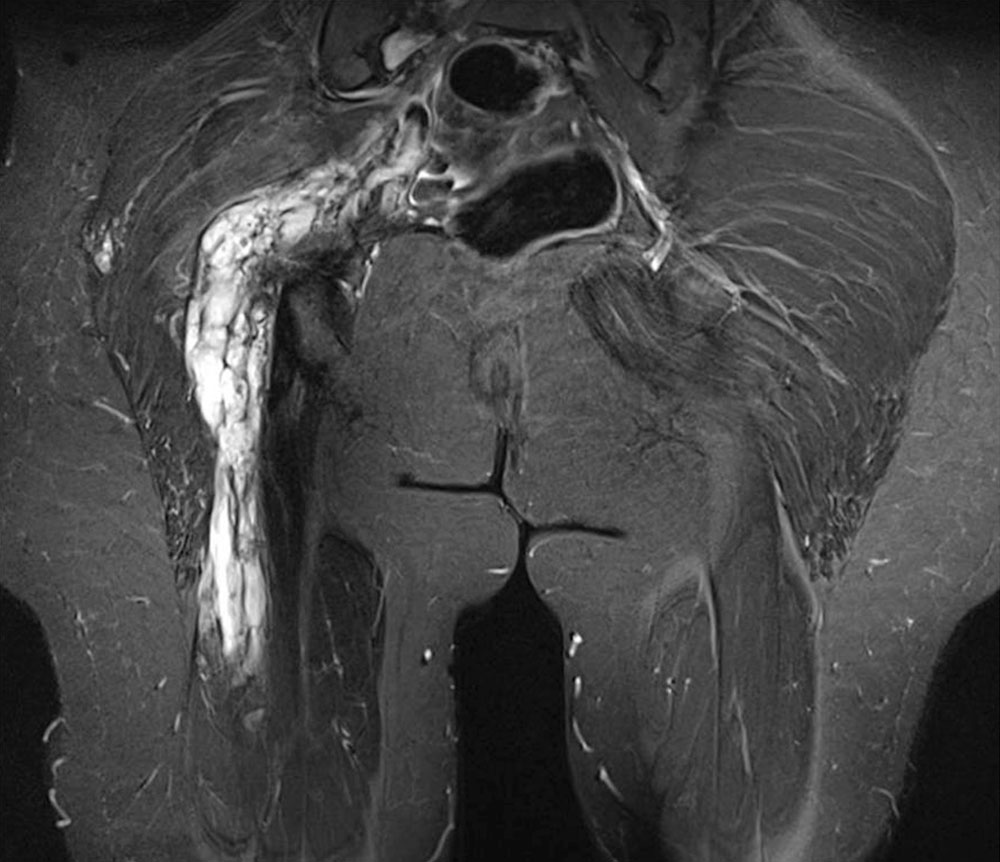

Abhängig vom Volumen der venösen Malformation kommt es zu einer Blutfüllung, die abhängig von der Position stärker wird und eine beschwerliche Spannung auslöst. Da das angesammelte Blut zudem wärmer als die umliegende Weichteile ist, verstärkt es die Beschwerden im Sinne eines „inneren Heizkörpers“. Die Lage der Malformation beeinflusst mit das Ausmaß der Kongestion und somit der Schmerzen, die als dumpf beschrieben werden. Bei vergleichbarem Volumen sind venöse Malformationen an den Beinen aufgrund des höheren hydrostatischen Drucks schmerzhafter als an den Armen oder im Gesicht. Innerhalb der Subkutis kann sich die venöse Malformation mehr ausdehnen und somit mehr mit Blut füllen. Innerhalb der Muskulatur hingegen, begrenzen die Muskelfaszie und der Muskeltonus das Ausmaß der Kongestion. Größere Malformationen, die vornehmlich subfaszial entwickelt sind, verursachen vergleichsweise wenig Schmerzen, insbesondere wenn sie von regelrecht entwickelter Muskulatur umgeben sind. Hingegen können kleinere, subfasziale venöse Malformationen in Knienähe oder an der Fußsohle starke, belastungsabhängige Schmerzen verursachen.

Der sehr langsame Blutfluss in einer VM kann aufgrund einer lokalisierten intravasalen Gerinnung zu einer umschriebenen Thrombosierung führen, die selten die gesamte Fehlbildung betrifft. In der Regel erreichen die sonographisch als ovaläre, echogene Strukturen nachweisbaren Thromben eine Größe von höchstens 10 bis 15 mm. Dennoch kann eine Phlebitis in einer VM sehr schmerzhaft sein. Es liegt ein Ruheschmerz vor, der durch Berührung und Druck verstärkt wird. Charakteristisch sind plötzlicher Beginn, stechender Charakter und Rückbildung innerhalb weniger Tage auf der Basis einer tatstbaren Verhärtung. Bei nur dünnkalibrigen Verbindungen zwischen den unreifen Gefäßen und den tiefen Leitvenen treten Thrombosen und Lungenembolien sehr selten auf. Große Verbindungen müssen verschlossen werden, da sie eine erhebliche Thrombemboliegefahr darstellen.